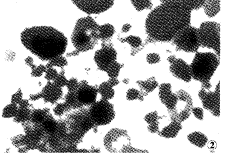

C、砷劑治療APL的機制:形態學上可見細胞核染質固縮形成凋亡小體。體外研究發現低濃度砷劑(0.1μmol/L)對NB4細胞有誘導分化作用在高濃度下(>0.5~1μmol/L),砷劑誘導凋亡。DNA分析,在細胞流式儀檢測中可見G1峰前出現凋亡峰DNA電泳示典型的凋亡梯形改變細胞及分子生物學研究結果顯示,As2O3可使PML/RARα融合蛋白降解BCL-2基因下調,對BAX基因無作用。以上結果提示As2O3治療APL的作用機制可能主要是誘導APL細胞凋亡,低濃度誘導分化此外砷劑作用中的一些分子機制包括: